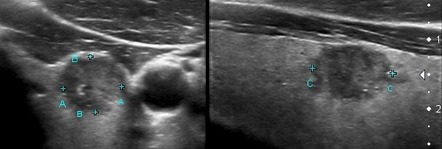

Фотографии опухоли медуллярной аденокарциномы

Раздел: Снимки-откровения